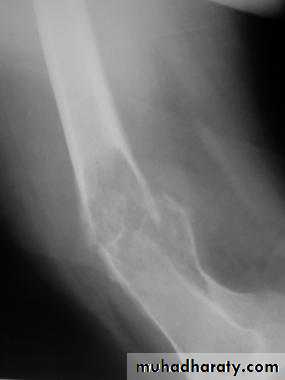

Supracondylar fractures of the femur

Typically the fracture occurs just proximally to the point where the medial and lateral cortices of the femur flare out to form condyles. In young it follow sever trauma and in old follow osteoporosis.A vertical extension of the fracture may split the two condyles apart in a T – shaped fracture line, and sometime there is more extensive comminuation.

Clinically :

pain and deformity in lower thigh after trauma.Knee is swollen and distal pulses should be palpated.

It may injured the popliteal artery and nerves.

Treatment :

These fractures can sometimes be treated successfully by traction through the upper tibia in young, followed by cast brace.

In old internal fixation is often preferable and the patient can get out of bed sooner (dynamic condylar screw and plate) .

Supracondylar fracture with its fixation by L – plate and screwsComplications